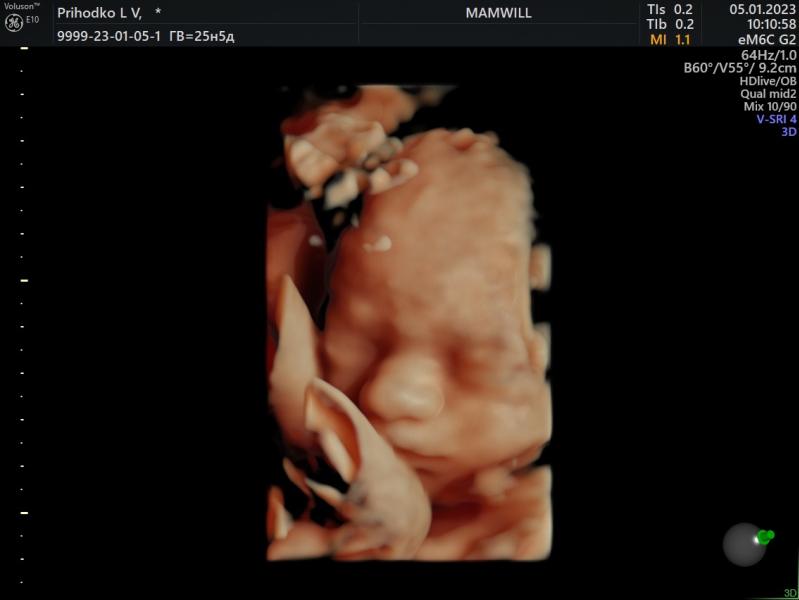

Наш долгожданный🤍

Были сегодня на встрече с мужем 🥰

Весит наш малыш 789 грамм

Сидим пока на попе с ногами на голове🙂

п.с. В конце его обидели уже🤧

05.01.2023